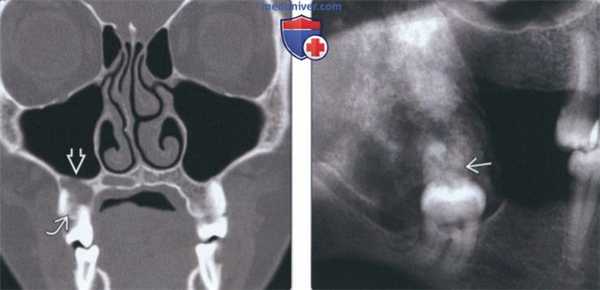

(Слева) На аксиальной КТ в костном окне у мужчины 78 лет в задних отделах верхней челюсти справа визуализируется КЭОО в виде купного экспансивною образования смешанной плотности. В опухоли определяются множественные мелкие разбросанные включения кальция, виден также крупный кальцинат.

(Справа) На аксиальной КТ в костном окне определяется КЭОО, занимающая правую верхнечелюстную пазуху, и прорастающая в полость носа справа (медиально) и крылонебную ямку (сзади).

(Слева) Накорональной КЛКТ визуализируется маленькая КЭОО у вершин корней премоляра справа. Между корнями зубов видны «нежные» кальцинаты. Обратите внимание на истончение дна верхнечелюстной пазухи.

(Справа) На панорамной рентгенограмме в задних отделах нижней челюсти справа визуализируется перикорональная КЭОО. Обратите внимание на сгруппированные кальцинаты в виде «свежевыпавшегог снега». Были обнаружены патоморфологические признаки злокачественности; в конечном счете опухоль привела к гибели пациента.